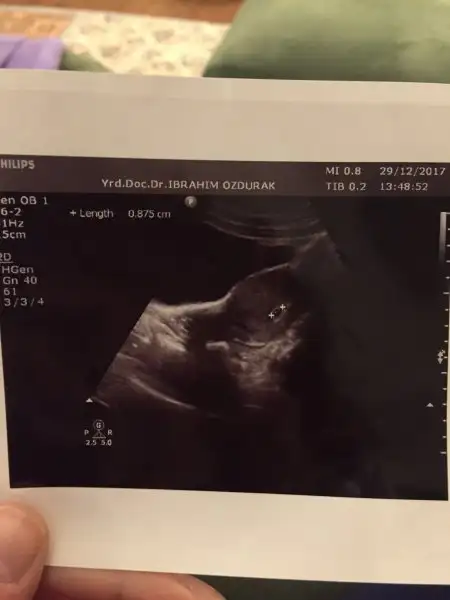

Hayirli olsun. Ramzi erkek diyor yine de Rabbim bilir. Bizim ki eglence sadece. Saglikla kucagina alirsin insallah.Yükleyebildim mi bilmiyorum ultrason görüntüsünü ilk kontrolüme bugün gittim. Nihayet gidebildim:) Keseyi gördüm kalp atışlarıda görülüyor dedi doktor ama dinletmedi. Ultrasondan oldum olası bişey anlamam.doktordan geldiğimden beri kağıtla bakışıp duruyorum

İyi geceler güzel anneler ve anne adayları diğer topicten buraya transfer ettim kendimiBiz de bugün keseyi gördük 5. haftamızdayız. Çok heyecanlı meselelermiş bunlar. Eşimle sabahtan beri bakıp duruyoruz minnacık bişey bu